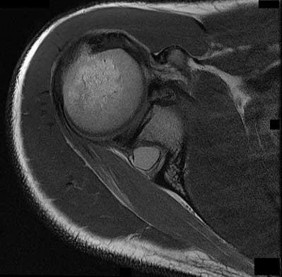

A 55-year-old man presents with an insidious onset of dull, aching shoulder pain. Radiographs demonstrate a calcified intramedullary lesion in the proximal humerus with endosteal scalloping involving 80% of the cortical thickness. Biopsy confirms a low-grade chondrosarcoma. What is the most appropriate definitive management?

Correct Answer: Wide surgical resection with anatomic reconstruction

Explanation:

The clinical and radiographic presentation is classic for a primary central chondrosarcoma. Unlike enchondromas, chondrosarcomas frequently exhibit endosteal scalloping greater than 2/3 of the cortical thickness and present with mechanical or biologic pain. Chondrosarcomas are notoriously resistant to both chemotherapy and radiation therapy. The mainstay of treatment for conventional chondrosarcoma is wide surgical resection. While extended intralesional curettage may be considered for some appendicular atypical cartilaginous tumors (Grade 1), wide resection is the gold standard, especially with significant endosteal scalloping and risk of cortical breakthrough.